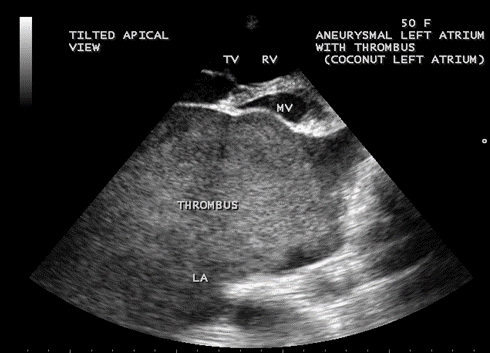

Case 5. Giant left atrium with dense SEC (spontaneous echo contrast) visible as massive thrombus occupying the entire giant left atrium and resembling as “coconut atrium” as shown in Figures 21 to 25 and movie in Figure 26

in rheumatic mitral stenosis in a 50- year old female. Patient was advised lifelong penicillin prophylaxis, Redo MVR (mitral valve replacement) and removal of thrombus with inverted T-shaped biatrial incision (endoatriectomy- transeptal superior approach)

Figure 22. Tilted apical view showing the thrombus occupying the entire Left atrium in a 50-year old female.

Figure 23. Tilted apical view showing the giant thrombosed left atrium in a 50-year-old female measuring as 203 x 176 mm.

Massive calcification of left atrium, predominantly affects the woman (74%) and it tooks an average duration of 19.7 years (17-20 years) to become manifest in rheumatic mitral stenosis and resembled a coconut shell [72]. The term ‘coconut atrium’ is misnomer to describe this condition and a complete opacification of giant left atrium with dense SEC seen as thrombus as shown in Figure 24, resembling a ‘coconut’ as in Figure 25 and this condition is better termed as ‘coconut atrium’ appropriately.